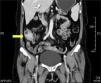

We present the case of a 58-year-old woman that sought medical attention for abdominal pain in the right flank of 2-month progression, changes in bowel habit with constipation, and a 5kg weight loss. Upon admittance her vital signs and laboratory tests were within normal limits. During physical examination a mass in the right iliac fossa was detected that was slightly painful upon palpation; there were no peritoneal irritation data. A strictured lesion in the cecum was encountered through colonoscopy. Biopsies were taken that only revealed nonspecific chronic inflammation. An abdominal tomography scan identified a 5cm tumor at the level of the cecum with thickening of the wall in the terminal ileum and the cecum, along with adenopathies (fig. 1). Because there was clinical suspicion of neoplasia, the patient underwent a laparoscopic right hemicolectomy. The intraoperative finding was peritumoral adenomegalies larger than 1cm. During macroscopic examination, a cecal appendix measuring 5 x 1.5cm was observed with thickened walls and fibroadipose obliteration of the lumen, along with a poorly delineated abscess-like lesion in the cecum. A pericecal abscess with extensive Actinomyces spp. colonization, «sulfur granules», and acute and chronic inflammation were viewed during the histopathologic study (fig. 2). Given these findings, 4-month therapy with amoxicillin plus clavulanic acid was begun. Postoperative progression was satisfactory and the patient was released 4 days after the surgery. Actinomycosis is a chronic suppurative disease that presents with the formation of fistula, sinus, inflammatory pseudotumor, or abscess. These are the characteristics that make it necessary to consider inflammatory bowel disease, inflammatory pelvic disease, and tuberculosis in the differential diagnosis. The infection can simulate malignancy due to its capacity to invade adjacent tissue and form masses.4–6 Up to 80% of the cases occur in women and 60% are associated with the use of an intrauterine device.2,4 The appearance of manifestations can take from months to years, given that the actinomycetes are slow-growing.1,2 Symptoms are nonspecific and in the majority of cases laboratory tests do not show abnormalities. Among the findings are normochromic anemia, leukocytosis, and increased globular sedimentation velocity. 2,7 Macroscopic examination of the surgical specimen of this case revealed inflammation at the level of the appendix. Actinomyces are normally found in stagnation zones, such as the cecum and appendix, the organs most frequently involved in the abdominal location.1,4,5 Early diagnosis of the acute appendicitis and opportune antibiotic therapy reduce the incidence of perforation, which is why inoculation through this inflammatory process is rare. Dissemination is mainly a result of tissue continuity; the hematogenic or lymphatic routes are less frequent, and so the presence of regional adenopathy is uncommon or is of late development.1,8 The peritumoral adenopathies in the present case made us suspect neoplasia as a first diagnostic possibility. The presentation of actinomycosis as a colonic mass suggestive of malignancy is infrequent (1%).4 Edema and mucosal ulceration can be found during colonoscopy, as well as umbilicated nodules, and in some cases, stricture. Contrast-enhanced tomography reveals extramural involvement and focal thickening of the colonic wall.9 Diagnosis through endoscopic or fine needle aspiration biopsies is complex, given that Actinomyces filaments are surrounded by widespread inflammation.5 Although preoperative diagnosis is useful for avoiding extensive resection, up to 96% of cases require surgical diagnosis. Through surgical management, the necrotic tissue is removed, fistulas are corrected, and the duration of antimicrobial treatment is reduced.3,4,10 Colonoscopy and tomography play an important role in the therapeutic follow-up. «Sulfur granules» are observed in the histopathologic study and they react to the Schiff and Grocott stains. Culture is complex and can be negative in up to 76% of the cases.5 The Actinomyces species is difficult to identify and the specific agent could not be recognized in our case. Nevertheless, they are susceptible to aminopenicillins and the combination with β-lactamase inhibitors should be considered first-line therapy. No disease recurrence is found after 4 months of treatment.10

In conclusion, actinomycosis should be included in the differential diagnosis of infiltrating tumors in the right colon, emphasizing the fact that in the majority of cases laboratory tests are normal and there are no adenopathies. A mass with attenuated focal areas invading adjacent structures is a characteristic finding in tomography scans. Even though Actinomyces normally reside in the appendix, there are few reports in the literature of cases in which appendicitis is the abdominal inoculation mechanism.